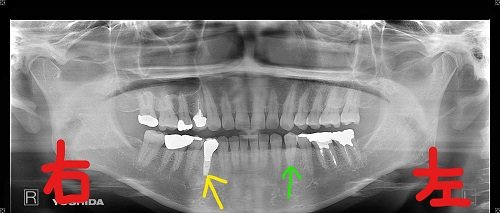

上記は、兵庫県三木市にお住まいの50代女性のレントゲン写真です。右下奥歯(黄色矢印)の被せ物が突然外れたため、当院を受診されました。症状として痛みや腫れはなかったものの、診査の結果、歯根に破折が見つかり、やむを得ず抜歯となりました。

下記写真は、抜歯後の右下小臼歯部にインプラント埋入を予定している状態のものです。被せ物が取れただけなのに抜歯が必要となった理由には、歯ぎしりや食いしばりによる長年の負荷が関係しています。

左下奥歯(緑色矢印)とその周囲の歯茎の張り出し(青色矢印)は、典型的な「骨の膨隆」であり、歯ぎしりが強い方によく見られる兆候です。歯科ではこのような口腔内所見を、咬合力の診断材料としています。

ちなみに、緑色矢印の歯とその前方の歯の間にできた隙間(白色矢印)は、歯ぎしりの影響により歯が移動した結果と考えられます。こうした症状は日常的に見られるもので、早期発見・早期対応が大切です。